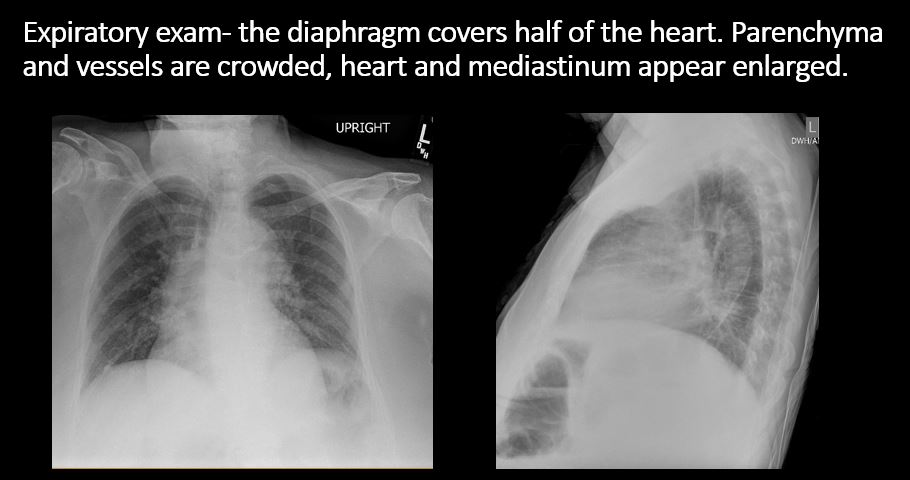

The exam is expiratory, rotated, over or under penetrated, or limited by overlying structures or soft tissues, body habitus, patient positioning, or motion. [Yes/No]

There is enlargement of the cardiac silhouette. [Yes/No]

There is elevation, depression, or contour abnormality of the right or left hemidiaphragm. [Yes/No]